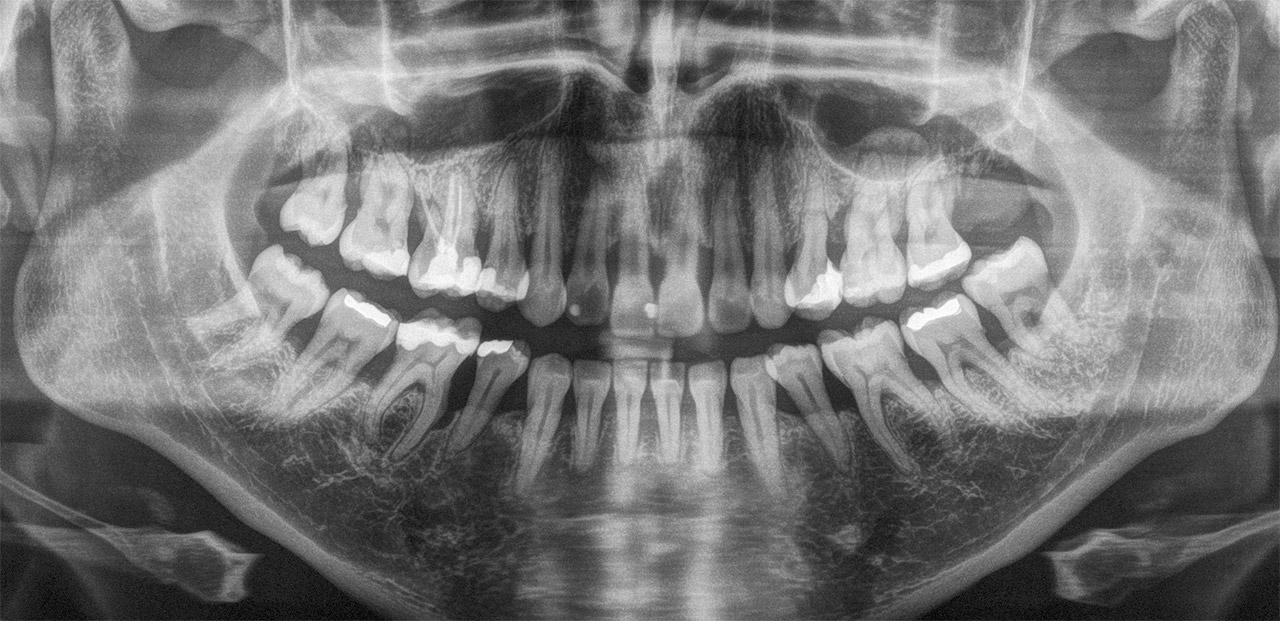

Die Parodontitis ist eine der häufigsten Erkrankungen der Mundhöhle. Sie ist vor der Karies (Zahnfäule) der häufigste Grund für Zahnverlust. Der Zahnhalteapparat leidet lokal oder generalisiert unter der Besiedlung krankmachender Bakterien und baut sich ab. Zähne werden beweglich und fallen aus. Unsere Maßnahmen stoppen die Parodontitis und verhindern den drohenden Zahnverlust.

Das bedeutet im Einzelnen: Intensive Parodontalbehandlung mit Ultraschall, Kürettage und Laser (siehe auch Laserbehandlung) zur Zerstörung des Biofilms; ggf. laborunterstütztes Screening des Biofilms (Bakterienabstrich) und in Ausnahmefällen auch eine gezielte systemische Antibiotika-Therapie; bei Bedarf parodontalchirurgische Intervention; kurzfristige Chlorhexidinapplikation (Full mouth desinfection) und Recall (engmaschige Kontrolle und Nachbehandlung).